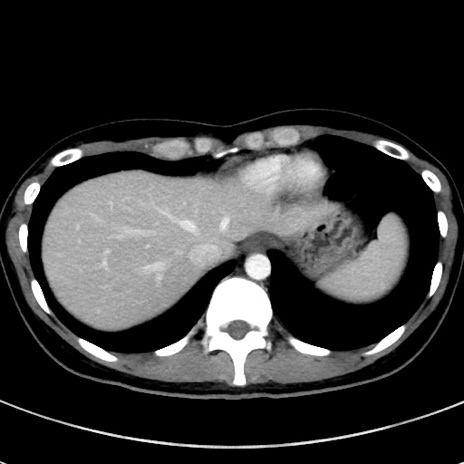

冠状断像

【症例】20歳代女性

【主訴】嘔吐、下腹部痛

【現病歴】昨日夕食後に嘔吐し下腹部痛が出現。本日になっても嘔吐持続し改善しないため来院。

【身体所見】意識清明、BT 37.2℃、BP 108/67mmHg、腹部:平坦、やや硬、下腹部正中から右にかけて圧痛あり、反跳痛軽度あり、tapping pain(+)。

【データ】WBC 13600、CRP 14.94